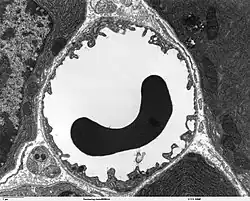

The vessels on the arterial side of the microcirculation are called the arterioles, which are well innervated, are surrounded by smooth muscle cells, and are 10-50 μm in diameter.[2] Arterioles carry the blood to the capillaries, which are not innervated, have no smooth muscle, and are about 5–8 μm in diameter. Blood flows out of the capillaries into the venules, which have little smooth muscle and are 10–200 μm. The blood flows from the venules into the veins. Metarterioles connect arterioles and capillaries. A tributary to the venules is known as a thoroughfare channel.

Most vessels of the microcirculation are lined by flattened cells of the endothelium and many of them are surrounded by contractile cells called pericytes. The endothelium provides a smooth surface for the flow of blood and regulates the movement of water and dissolved materials in the interstitial plasma between the blood and the tissues. The endothelium also produces molecules that discourage the blood from clotting unless there is a leak. Pericyte cells can contract and decrease the size of the arterioles and thereby regulate blood flow and blood pressure.